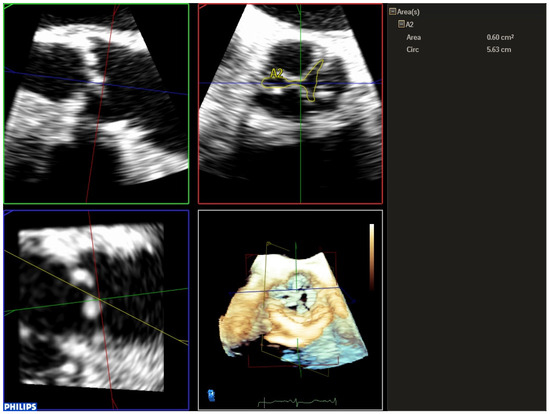

| 1 | Three-dimensional TEE allows us to accurately evaluate the aortic valve morphology and measure the valve annulus prior to TAVR implantation, helping us to choose the appropriate size of the prosthesis, especially useful in cases where the cardio-CT is not of adequate quality. |